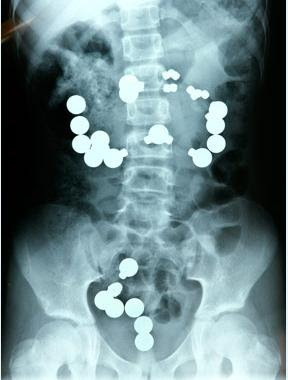

1. Lance Armstrong "bersekrup"

Ini adalah gambar sinar-x selangkangan juara Tour de-France, lance armstrong.